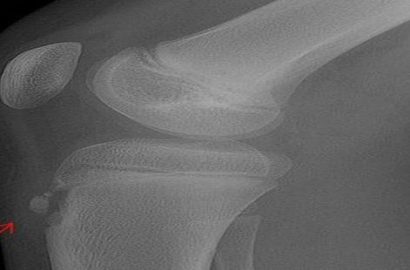

リンパ節は全身で800箇所以上あるともいわれ、中でも、鎖骨 の上、頸部、腋窩、鼠蹊部、膝の裏には大きい節があります。